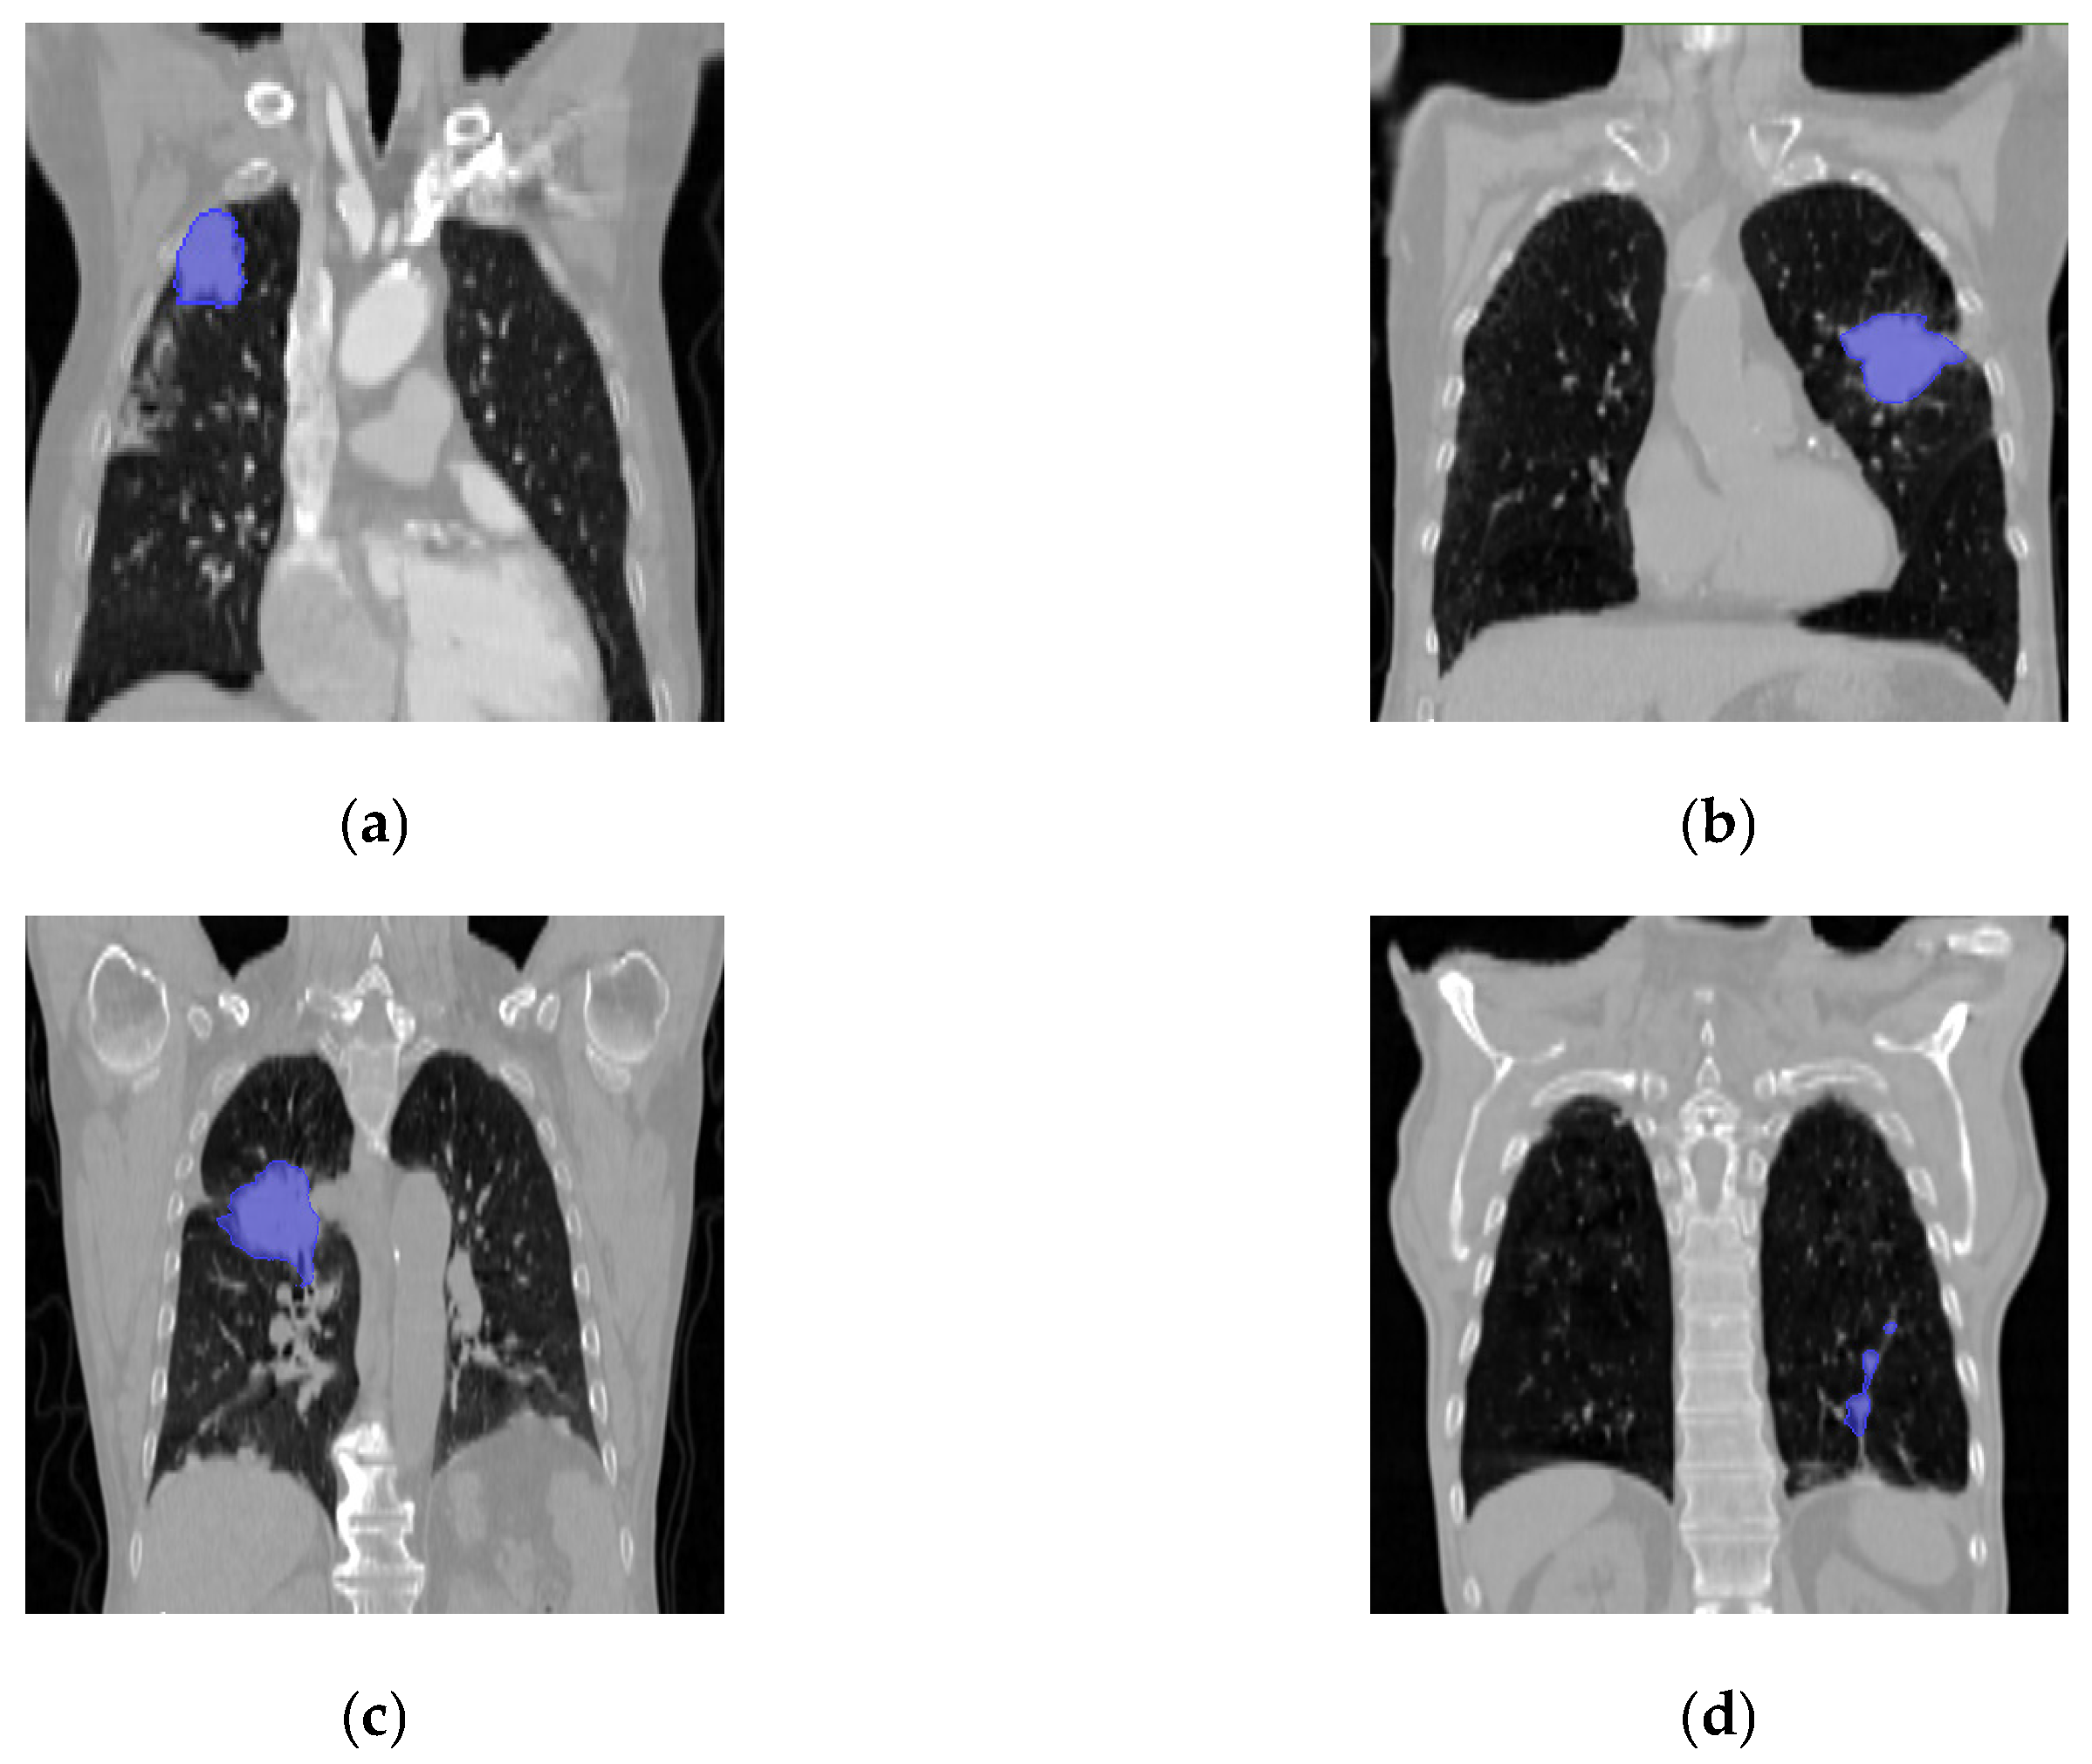

3. Data Preprocessing and Experimental Parameter Settings